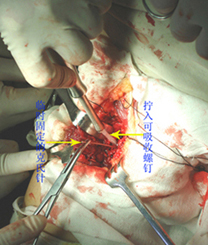

标题: 手术证实的结果。

手术证实是后交叉韧带胫骨附着处撕脱骨折。

术中用可吸收螺钉固定。